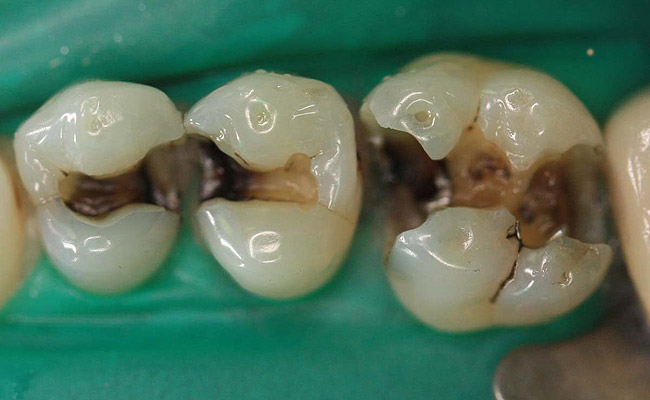

Case 2 (Figure 7 through Figure 11) depicts a series of defective amalgams on the first molar and biscupids. The amalgams were removed, the decay was excavated and cracks were eliminated. Bonding was completed on dentin and enamel. The teeth were matrixed and composite was built with layering techniques. To control contours, each tooth was completed individually, and then the next one was done. Composite was shaped, occlusal adjustment was completed, and final polishing was done.

Figure 7. Three defective amalgams and cracks on the first molar and bicuspids.

Figure 7

Figure 8. Teeth after removal of amalgams.

Figure 8

Figure 9. Prepared teeth after removal of decay and cracks.

Figure 9